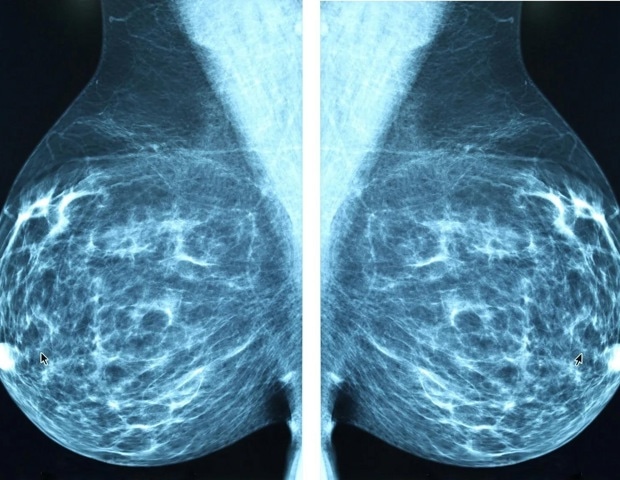

Νέα κατεύθυνση για τη μαστογραφία στις γυναίκες από 50 έως 74 ετών

Μια πρόσφατη οδηγία από το American College of Physicians (ACP) προτείνει ότι όλες οι ασυμπτωματικές γυναίκες, που βρίσκονται σε κανονικό κίνδυνο και είναι ηλικίας 50 έως 74, θα πρέπει να υποβάλλονται σε διετή μαστογραφία για τον καρκίνο του μαστού. Για τις γυναίκες ηλικίας 40 έως 49 ετών, προτείνεται να συζητήσουν με τον γιατρό τους σχετικά με τον προσωπικό τους κίνδυνο αλλά και τα πλεονεκτήματα και τις επιπτώσεις της εξέτασης αυτή.

Η προσοχή πρέπει να δοθεί στις πιθανές βλάβες του διαγνωστικού ελέγχου, όπως είναι τα ψευδώς θετικά αποτελέσματα, η ψυχολογική πίεση που δημιουργείται από αυτά, η υπεδιάγνωση και οι υπερθεραπείες. Αυτοί οι παράγοντες μπορεί ενδεχομένως να υπερβαίνουν τα άγνωστα οφέλη για τις γυναίκες σε αυτή την ηλικιακή ομάδα. Η οδηγία αυτή με τίτλο “Screening for Breast Cancer in Asymptomatic, Average-Risk Adult Females: A Guidance Statement from the American College of Physicians” δημοσιεύθηκε στο περιοδικό Annals of Internal Medicine.

Συμπληρωματικές εξετάσεις για γυναίκες με πυκνές μαστούς

Για τις γυναίκες που είναι ασυμπτωματικές και έχουν πυκνούς μαστούς, το ACP προτείνει στους γιατρούς να εξετάσουν τη χρήση συμπληρωματικής ψηφιακής τομοσύνθεσης (DBT). Οι αποφάσεις αυτές θα πρέπει να λαμβάνουν υπόψη τα πιθανά οφέλη και τις βλάβες, την έκθεση σε ακτινοβολία, τη διαθεσιμότητα, τις προτιμήσεις των ασθενών και το κόστος. Ωστόσο, η χρήση συμπληρωματικής μαγνητικής τομογραφίας (MRI) ή υπερήχων για την εξέταση αυτή δεν συνιστάται.